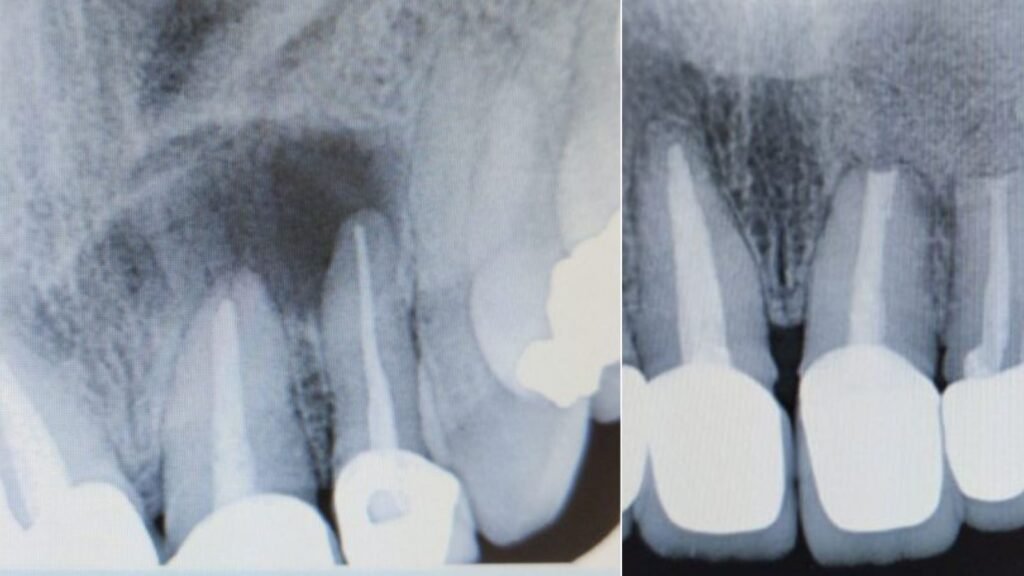

Todo comienza con una evaluación detallada del diente y del área afectada. Realizamos estudios radiográficos específicos para localizar con exactitud la lesión en la punta de la raíz y evaluar el estado del hueso circundante. Analizamos tratamientos previos, síntomas actuales y el pronóstico del diente. Durante esta fase, te explico de forma clara por qué la apicectomía es la mejor opción en tu caso y qué resultados puedes esperar. Nuestro objetivo es que comprendas completamente el diagnóstico y tomes la decisión con seguridad y tranquilidad.

El procedimiento se realiza bajo anestesia local para asegurar una experiencia cómoda. Accedemos cuidadosamente a la zona del ápice, retiramos el tejido infectado y seccionamos la punta de la raíz afectada. Posteriormente, sellamos el extremo radicular para impedir la reaparición de bacterias. La cirugía se realiza con técnicas precisas y mínimamente invasivas, reduciendo el impacto en los tejidos y favoreciendo una mejor cicatrización.